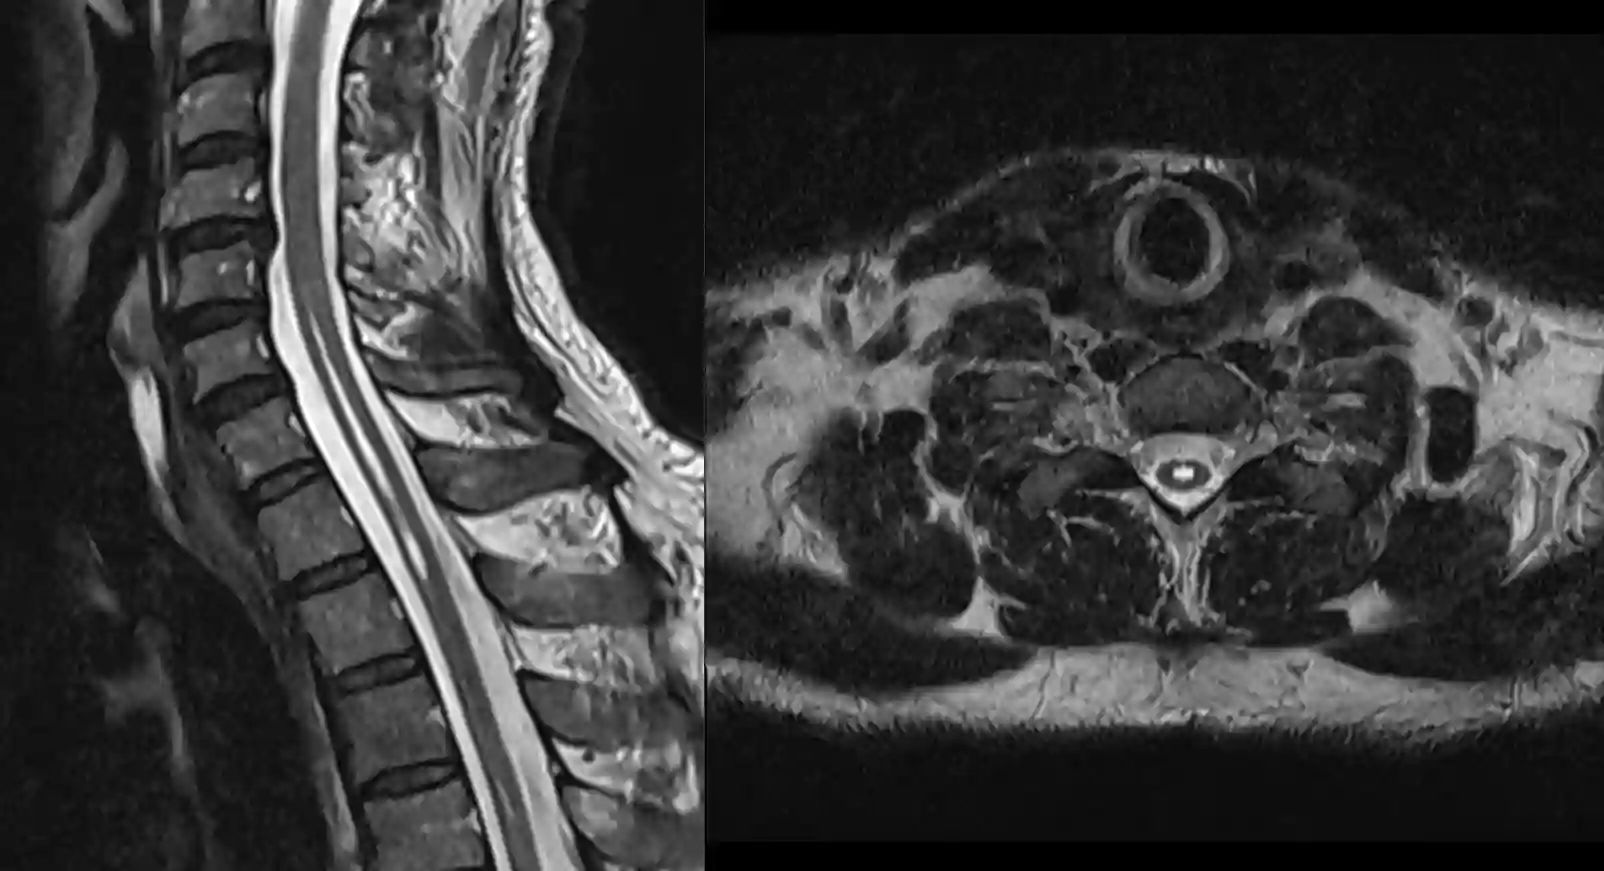

Der Goldstandard für die Darstellung einer Syringomyelie ist eine MRI Bildgebung.